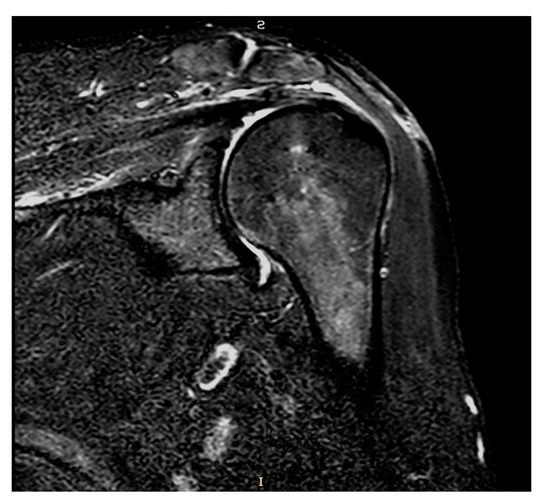

The edges of the RC tear were identified and debrided; tendon mobilization was attempted to verify if a primary tendon-to-bone repair was possible. When re-insertion to the footprint was possible, but the tendon tissue quality was clinically considered poor, a patch was sutured with non-absorbable stitches on the bursal side of the RC and reinserted together with the tendon onto the respective tuberosity over the anchors (Figure 1). The RC tendon was retracted and non-mobilizable, confirming the impossibility of a direct tendon-to-bone repair sutured to the edges of the tendon stump with non-absorbable sutures and then reinserted into the tuberosity with anchors (Figure 2). In both techniques (augmentation and bridging), and with both the biological implant (xenograft of collagen of porcine origin and DED-LYO allograft), the patch was cut to the appropriate size corresponding to the gap to be reinforced or covered. To control bleeding, in the absence of contraindications, tranexamic acid was administered both intravenously and locally, as previously described [17].

Figure 1. DED-LYO patch augmentation procedure.

Figure 4. Coronal STIR-weighted MRI.